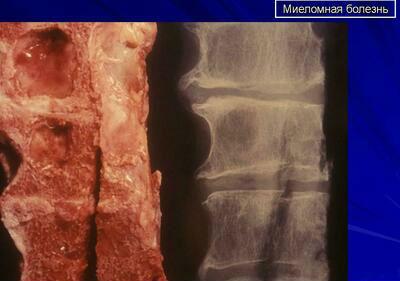

При опухолевом поражении В-лейкоцитов, то есть иммунных клеток возникает заболевание группы парапротеинемических лейкозов – миелома. Множественные опухоли могут привести к разрушению костной ткани из-за злокачественного размножения клеток плазмы в костном мозге, так как плазматические клетки начинают создавать переизбыток иммуноглобулина.

- Боли в костях. Наиболее часто они локализуются в позвоночнике и ребрах. Дискомфорт усиливается при физической активности.

- Искривление позвоночника;

- Спонтанные переломы;

- Рентгенологическое исследование костей;

- Разрушение костей.